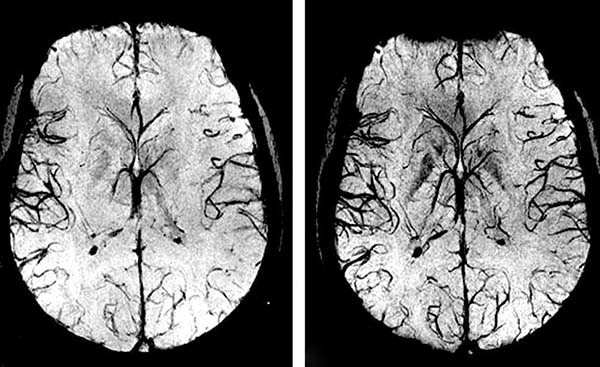

Przez 1,5 miesiąca przyjmowania Cardiotonus przywracane jest krążenie krwi o 99,71%.

Krążenie krwi zostaje przywrócone systemowo – we wszystkich naczyniach, tętnicach i naczyniach włosowatych.

Cardiotonus to know-how, duma naszych naukowców. Zapewnia prawie 100% oczyszczenie naczyń krwionośnych dzięki aktywnym frakcjom CO2 ekstraktów, które wnikają w blaszki cholesterolowe i rozpuszczają je od wewnątrz.

Rozpuszcza blaszki miażdżycowe, skrzepy krwi i wapń. Zwiększa światło naczyń krwionośnych do 99,71% normy i przywraca krążenie krwi.

Zapobiega to tworzeniu się nowych płytek i 11-krotnie zmniejsza ryzyko udaru.